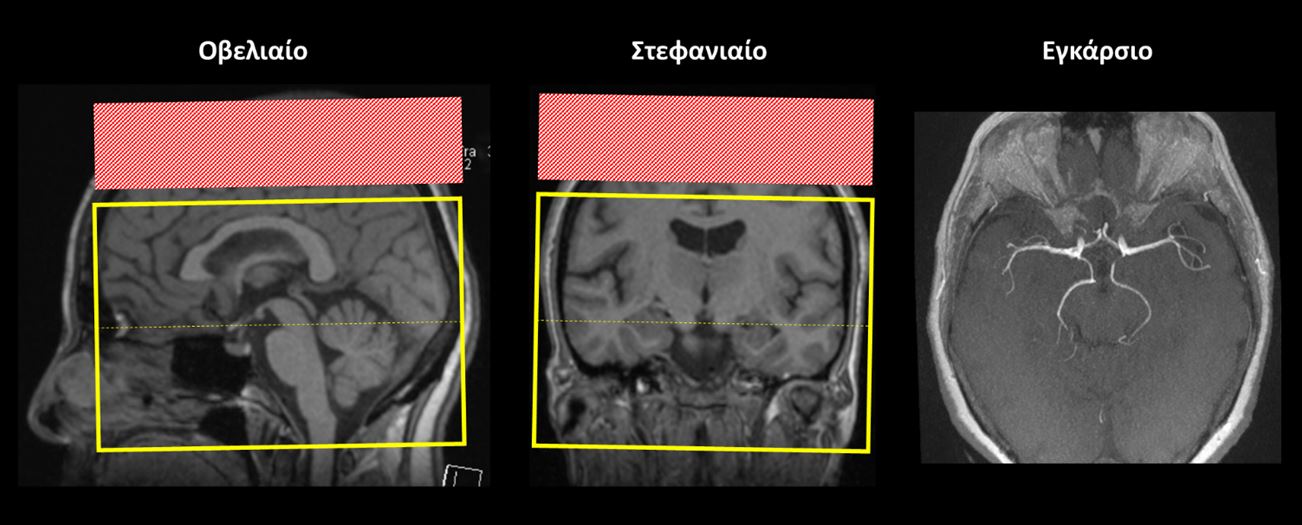

Εγκάρσιο (Axial/Transversal) ολόκληρου του εγκεφάλου: οι εγκάρσιες τομές σχεδιάζονται παράλληλα με το πρόσθιο (γόνυ) και το οπίσθιο (σπληνίο) κέρας του μεσολοβίου στο οβελιαίο επίπεδο και κάθετα στη μέση γραμμή του εγκεφάλου στο στεφανιαίο επίπεδο. Οι τομές πρέπει να περιλαμβάνουν ολόκληρο τον εγκέφαλο έως και την παρεγκεφαλίδα (κάτω).

Εγκάρσιο (Axial/Transversal) ολόκληρου του εγκεφάλου: οι εγκάρσιες τομές σχεδιάζονται παράλληλα με το πρόσθιο (γόνυ) και το οπίσθιο (σπληνίο) κέρας του μεσολοβίου στο οβελιαίο επίπεδο και κάθετα στη μέση γραμμή του εγκεφάλου στο στεφανιαίο επίπεδο. Οι τομές πρέπει να περιλαμβάνουν ολόκληρο τον εγκέφαλο έως και την παρεγκεφαλίδα (κάτω). Πρέπει να γίνεται χρήση παλμού χωρικού κορεσμού άνωθεν των τομών (κόκκινο ορθογώνιο πλαίσιο) με σκοπό την απομόνωση της αρτηριακής ροής. Οι τομές πρέπει να περιλαμβάνουν τα αγγεία του κύκλου (ή πολυγώνου) του Willis. Τυπικά, οι τομές πρέπει να καλύπτουν από το μεσολόβιο (πάνω) έως και το ινιακό τρήμα (κάτω).